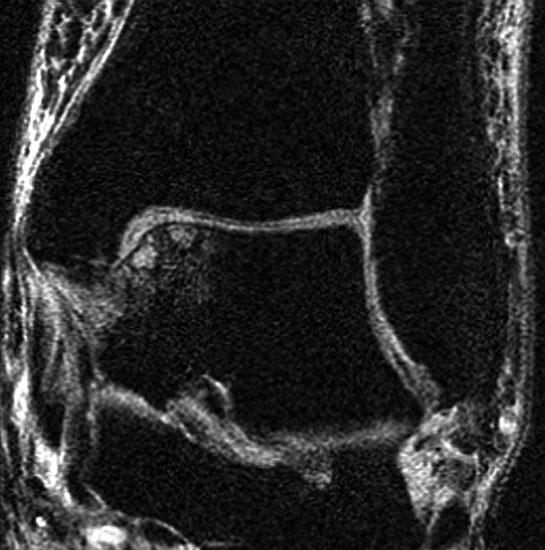

Die Standardsequenzen umfassen Fast-Spin-Echo (FSE) und Gradientenechosequenzen 22. Die Pulssequenzen umfassen typischerweise Protonendichte (PD) und fettunterdrückte Protonendichte Sequenzen (PD-FS) 17. In unserem eigenen Protokoll verwenden wir aktuell isotrope 3D-Gradientenechosequenzen (true FISP) (Abb. 3), protonendichte-fettunterdrückten Turbo-Spin-Echo-Sequenzen (PD-FS-TSE) (Abb. 4 und 5) und T1-gewichtete Spinechosequenzen (Abb. 6). Wichtig ist letztendlich die räumliche Auflösung als Funktion der Schichtdicke, dem Blickfeld (FOV) und der Bildmatrix 17.